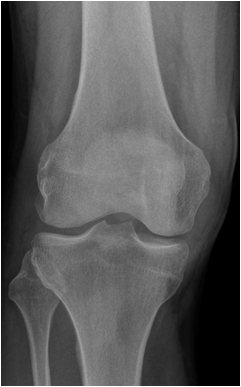

Primary osteoarthritis involves weight bearing joints such as the knee, where changes are seen especially in the medial compartment and the patellofemoral compartment. In the hip changes are seen superolaterally. The tibiotalar joint is rarely significantly involved, except for changes along the anterior margin of the distal articular surface of the tibia. These are most likely posttraumatic in origin.

Fig. 13. A) Knee joint with degenerative changes. Note the sclerotic medial tibial plateau and joint space narrowing. A small osteophyte is seen on the medial femoral condyle. B.) Pelvis with marked degeneration of both hip joints. The right femoral head shows lateral osteophyte formation and is deformed. The joint space is narrow with increased subchondral sclerosis of the acetabular roof. The left hip has a marked joint space narrowing and lateral osteophyte formation. The femoral head shows increased density due to sclerotic areas and irregularity.